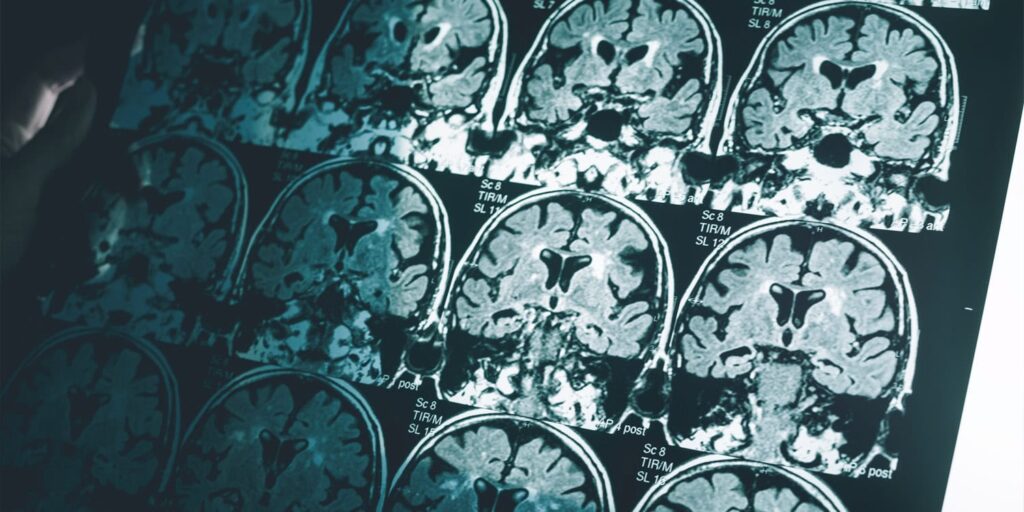

A groundbreaking brain imaging study has revealed that men experience a slightly greater age-related decline in brain structure compared to women. This finding challenges the prevailing notion that brain aging patterns contribute to the higher prevalence of Alzheimer’s disease in women. The research, published in the Proceedings of the National Academy of Sciences, offers new insights into the complex dynamics of brain aging.

The study, conducted by an international team led by the University of Oslo, utilized an extensive dataset comprising 12,638 MRI scans from 4,726 cognitively healthy participants aged 17 to 95. The longitudinal nature of the data, with individuals scanned at least twice over an average interval of three years, allowed researchers to track brain changes over time.

Initial analyses revealed that men experienced a steeper decline than women in 17 different brain measures, including reductions in total brain volume, gray matter, and white matter. Men also exhibited faster thinning of the cortex in visual and memory-related areas. After adjusting for head size, the pattern largely persisted, with men showing a greater rate of decline in specific brain regions.